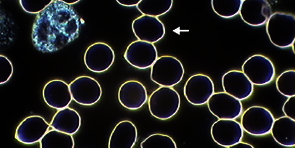

Rote Blutkörperchen (Erythrozyten)

Aussagekräftig sind Anzahl, Größe, Form, Oberflächenbeschaffenheit, Beweglichkeit und Inhalt dieser Blutzellen.

- Gesunde, intakte Erythrozyten

- Patologisch veränderte Erythrozyten durch extreme Säurebelastung des Blutes